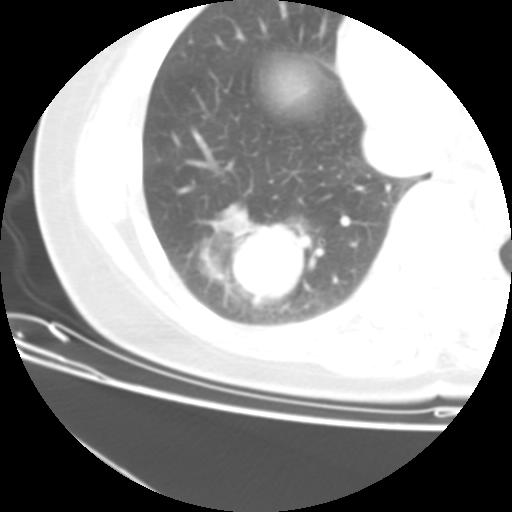

女 46岁,咳嗽咳血10月

【linyiming】右肺下叶见类圆形软组织影,边缘欠规整,略分叶状。考虑炎症假瘤可能?

未排除周围型肺癌。建议CT增强。

【aosangwa】肺癌的主要特征是:毛刺征、分叶征及胸膜凹陷征,此病例位于右肺下叶距胸膜很近,但没有胸膜凹陷征,其周围像示渗出性病变,病灶在两窗上没有大小没有发生大小改变。

考虑其良性肿瘤,炎性假瘤可能性大,其主要鉴别是:结核球、周围型肺癌、血管瘤

病理诊断类癌(周围型)。